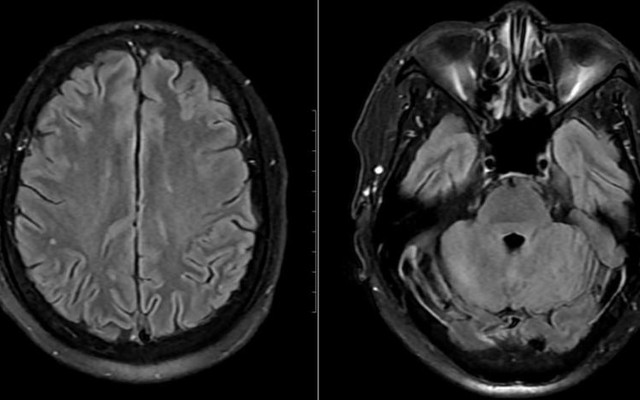

Sống khỏe 2025-08-22T07:25:00Sau khi chế biến thịt lợn sống, người đàn ông sốt, mệt mỏi, đến viện xét nghiệm được chẩn đoán nhiễm liên cầu khuẩn lợn.

Sống khỏe 2025-07-09T18:30:00Mới đây, một người đàn ông ở Hà Nội đã nhập viện trong tình trạng nguy kịch, nổi nhiều ban tím ở đầu, mặt, tai, tứ chi và phải thở máy sau khi ăn các món chế biến từ lợn.

Sống khỏe 2024-07-18T18:04:00Một người đàn ông ở Thanh Hóa đã phải nhập viện cấp cứu trong tình trạng sốt cao, nổi các ban xuất huyết trên da sau khi chế biến thịt lợn.

Sống khỏe 2024-06-20T16:31:00Bệnh nhân nhập viện trong tình trạng phù toàn thân, nhiều ban xuất huyết hoại tử toàn thân - mặt, suy đa cơ phủ tạng, tổn thương gan, thận, rối loạn đông máu…